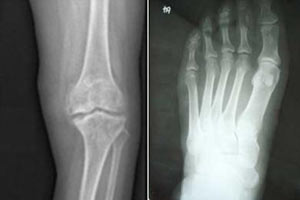

(图:程先生治疗 后的跖趾、膝关节X光)

第一个疗程结束后,程先生的左膝关节疼痛减轻,僵硬感有所缓解,双足第一跖趾红肿消退不少。第二个疗程结束后,程先生的左膝关节红肿消退,僵硬感消失,双足第一跖趾关节肿胀消失,按压还有微痛感,能自由活动。第三个疗程结束后,程先生左膝及双足第一跖趾关节红肿痛全部消失,蹲起轻松自如,腰椎部也不疼了,整个人精神不少。